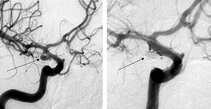

Um ein Aneurysma darstellen zu können, braucht man spezielle Techniken. Manchmal kann man das Aneurysma anhand eines CT-Scans oder besser noch eines Kernspintomogramms (MRT) annäherungsweise vermuten. Zur genauen Beurteilung der Anatomie und der weiteren Behandlungsmöglichkeiten ist jedoch eine CT-Angiographie oder eine Gefäßdarstellung mittels konventioneller Angiographie notwendig.

links: Angiographische Darstellung eines Aneurysmas

rechts: Dreidimensionale Darstellung des gleichen Aneurysmas